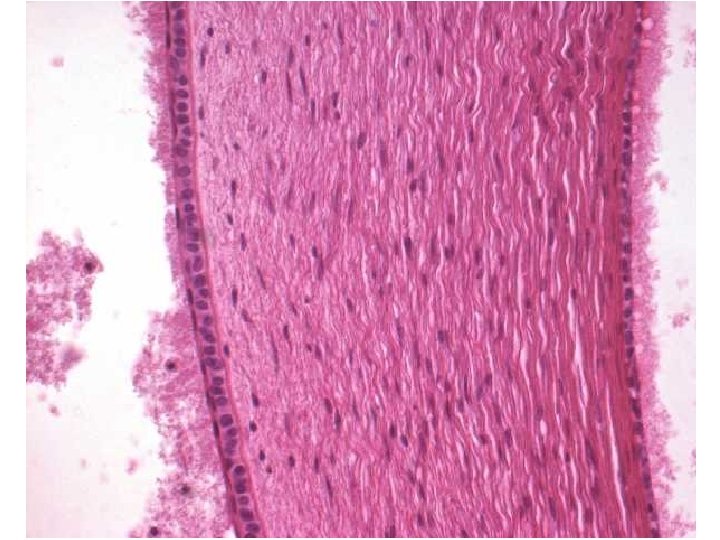

Tunica vasculosa (media) Cévnatka = Choroidea • lamina suprachoroidea (= lamina fusca sclerae) • spatium perichoroideum • lamina vasculosa (choroidální stroma) – velké cévy, vazivo, hladké svalové buňky, nervíky • lamina choroidocapillaris – kapiláry • lamina basalis = Bruchova membrána – BM pigmentového epitelu a kapilár + vazivo

Tunica interna (nervosa) = Sítnice = Retina • pars caeca – pars iridica – pars ciliaris • ora serrata • pars optica – 11 vrstev – pigmentová část – senzorická část

Sítnice – pigmentová část • stratum pigmentosum • jednovrstevný kubický epitel • buňky (pigmentocytus) spojeny těsnými spojeními • apikální části obsahují melaninová granula • obklopují vnější segmenty senzorických buněk • interfotoreceptorová matrix výživa buněk, obnova fotopigmentu, degradace membranózních disků

Tunica sensoria (interna) Vrstvy zrakové části sítnice • celkem 11 vrstev !!! neděste se !!!

Tunica sensoria (interna) Vrstvy zrakové části sítnice • stratum pigmentosum (1. ) • stratum nervosum (2. -10. ) – stratum segmentorum externorum et internorum(2. ) – stratum limitans externum (3. ) – stratum nucleare externum (4. ) – stratum plexiforme externum (5. ) – stratum nucleare internum (6. ) – stratum plexiforme internum (7. ) – stratum ganglionicum (8. ) – stratum neurofibrarum (9. ) – stratum limitans internum (10. )